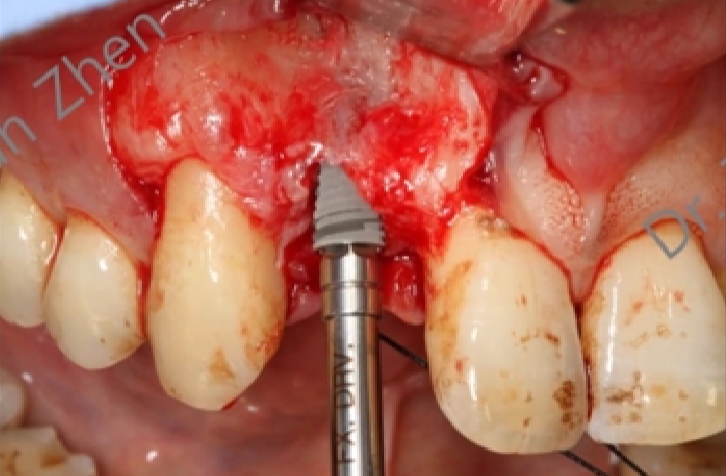

术中技巧:

-

在即刻种植完成后,我们从腭侧相邻位置采取软组织,制作一个旋转瓣。

这个旋转瓣带有一个蒂部,保留了一部分血液循环,以减少组织坏死的风险。

旋转瓣通过转换位置,覆盖填补即刻种植后留下的牙槽窝。

这一过程有助于局部骨增量的完成,即在种植区域增加骨组织,以支持种植体的稳定性。